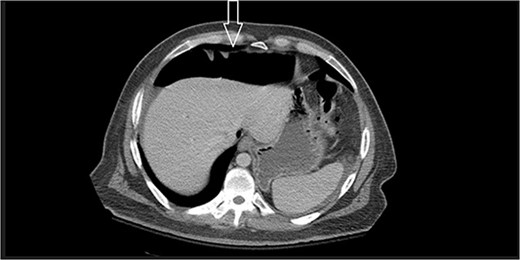

Ten days after discharge, he was readmitted with the same symptoms of nausea and vomiting. The CT showed pneumoperitoneum (see Fig. 2) again with another EL with consequent negative results and no viscus perforations. Lesser amounts of free fluid in both upper quadrants and in the pelvis were noted. These findings remain suspicious for a perforated viscus. Few days later, the patient reported feeling better and was discharged.